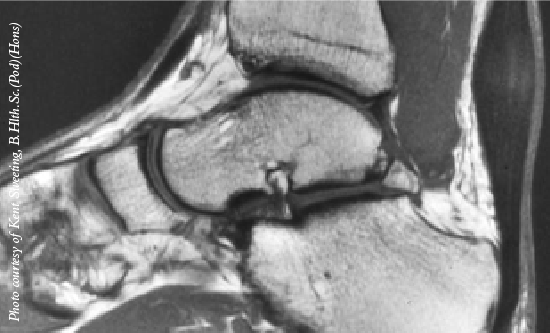

Study Says Arthroscopic Debridement Is Effective For Anterior Ankle Impingement

Patients who have anterior ankle impingement without osteoarthritis fare well postoperatively after arthroscopic debridement, according to a recent study in the American Journal of Sports Medicine.

The study examined 46 patients with anterior ankle impingement and no ankle osteoarthritis who had persistent ankle pain and activity restrictions following at least six months of non-operative management. The patients had standardized arthroscopic debridement and a minimum follow-up of five years.

Although patients demonstrated limited improvement in ankle dorsiflexion, going from a mean 24.7 degrees to 27 degrees, researchers noted substantial improvement in the Foot Functional Index from a mean 20.5 to 2.7. However, authors did note that 84 percent of patients had recurrence of radiological osteophytes.